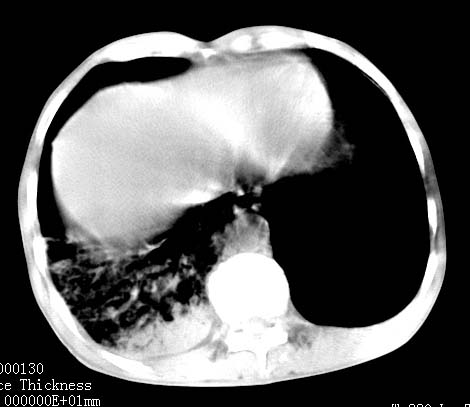

病人女 60岁 咳嗽 气促十余天,大叶性肺炎.

右肺上下叶均见 大片状密度增高影,边界清晰,其内可见支气管充气征,气管支气管通畅。纵膈略向右移位,其内无肿大淋巴结影。首先考虑炎性病变。不排除一些特异性的炎症。不知道发烧吗??wbc高吗??建议治疗后复查!!